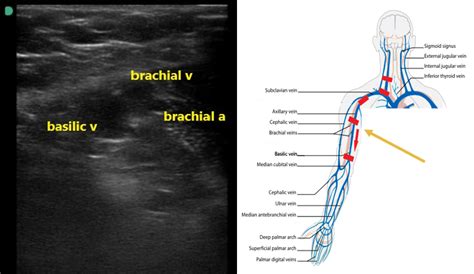

Forest Pruitt Blog